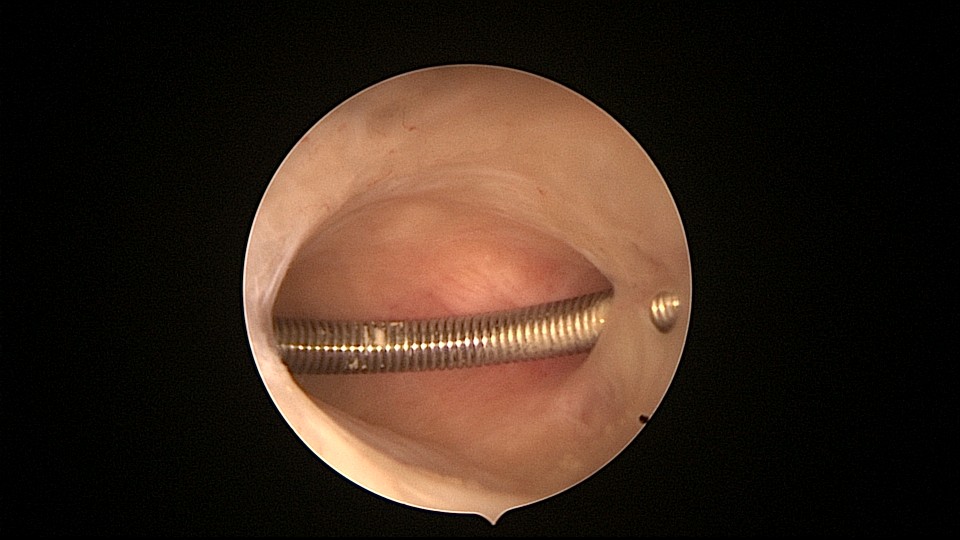

患者81岁,G5P5,顺产5次,安环50年,绝经23年,高血压病史多年,10年前因颅内肿瘤行开颅手术,4年前行腹腔镜胆囊切除术,外院介绍到我院宫腔镜取环。子宫前位,宫颈萎缩,穹隆展平,宫颈外口位于穹隆偏左侧,平滑狭小,夹持宫颈很困难,阴道内镜方式进入宫腔,见宫腔下部O型环圈内前后壁粘连,顿性分离粘连,宫腔中上部O型环与两侧宫壁嵌顿,异物钳松动节育环,但难以取出,取环钩沿镜鞘外侧进入宫腔,配合中弯钳牵拉出节育环,环变形,检查环完整,宫腔无其他异常。